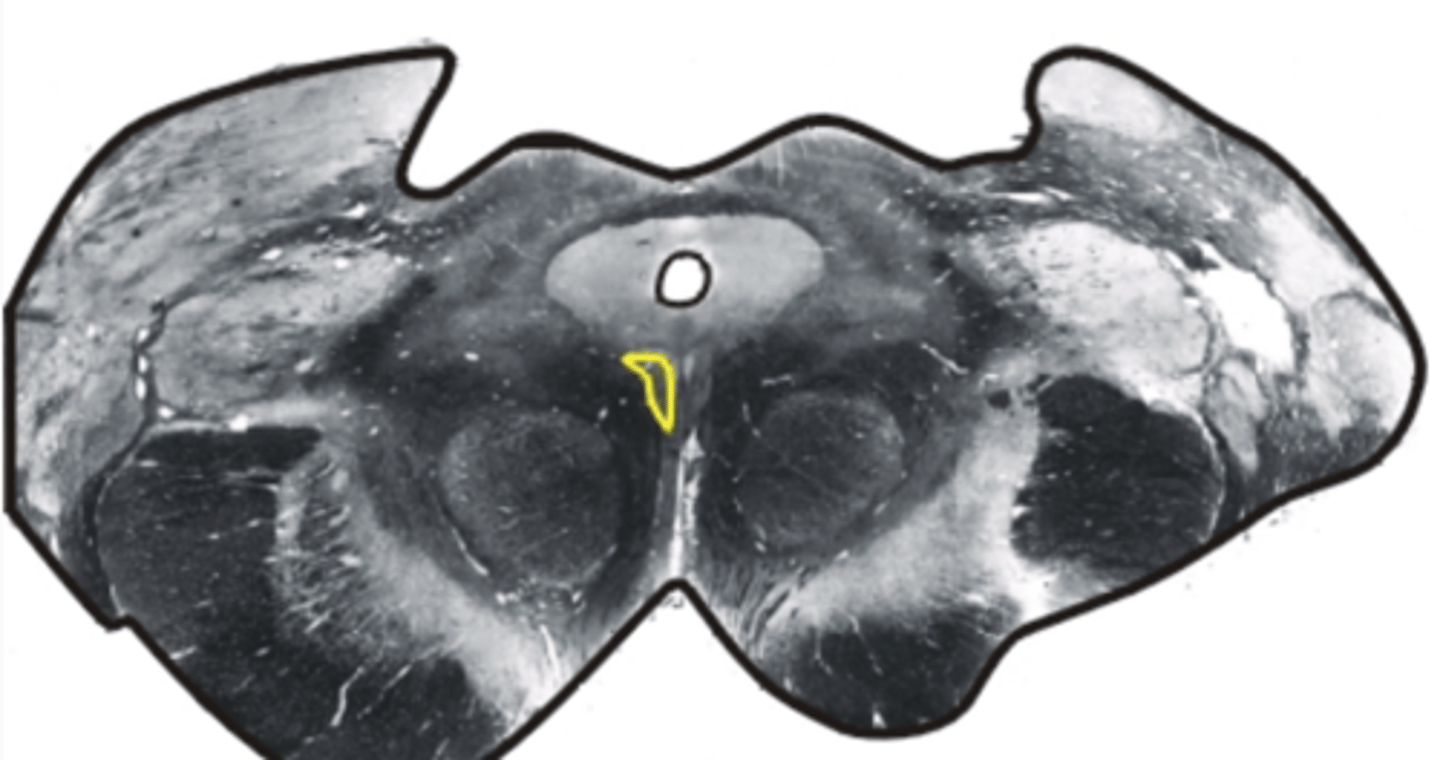

oculomotor nucleus in the midbrain

controls eye movements & pupillary constriction

trochlear nucleus

controls superior oblique eye muscles

Edinger-Westphal nucleus

part of oculomotor complex controlling ciliary muscle for accommodation of the lens & pupil constriction